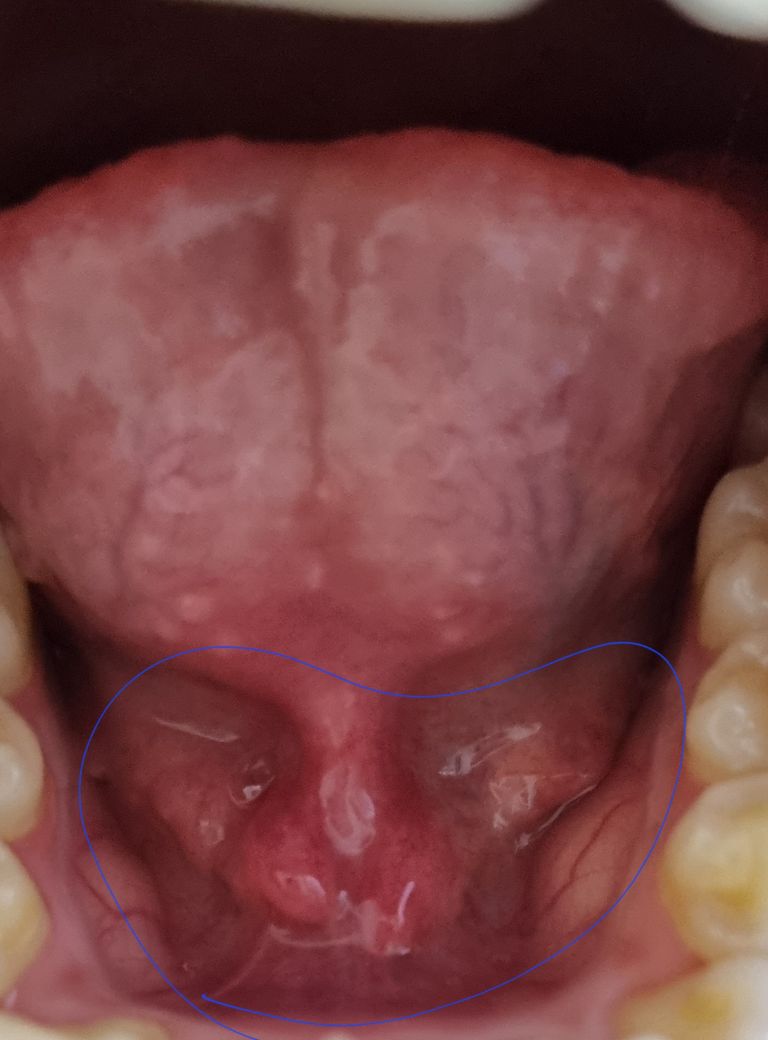

2주 전에 여행을 다녀와서 감기를 심하게 걸렸습니다. 약을 계속 복용하고 이젠 약을 다 먹었고, 증상도 호전되어 약을 복용하지 않게 되었는데, 2주째 꾸준히 목이 아픕니다. 지금 증상으로는 가래가 약간 있고 침 삼킬 때 통증이 있고, 목이 쉬기도 하고, 목 통증도 있습니다. 그런데 오늘 갑자기 혀 밑이 아프면서 첨부된 사진과 같이 파란색 원에 표시된 쪽에 이물감이 느껴지기 시작하면서 아프더군요. 그래서 혀를 쭉 빼봤더니 안쪽까지 아팠습니다. 혹시 이 목아픔이 목이 아픈 게 아니라 혀가 아파서 아팠던 걸까요? 요근래 목이 자주 쉬었고, 목 아픈 게 호전될 기색이 안 보이는데 혹시 큰 병일 수도 있을까요... 암 같은...

• 1번 째 사진

감기나 감염 후에 생긴 잔여 증상, 혀 밑샘(설하선)의 문제, 또는 기타 점막의 손상 또는 염증 등이 있을 수 있습니다. 악성종양과 관련이 있을 가능성은 높지 않습니다.

혀 밑 통증과 함께 가래, 삼킬 때의 통증, 목소리 변화 등의 증상이 있다면, 이는 상기도 감염, 후두염, 인두염 등을 포함한 다양한 상태를 반영할 수 있습니다. 특히, 통증이 지속되고 증상이 호전되지 않는 경우, 더 심각한 상태일 가능성도 배제할 수 없으므로 의료 전문가의 진단을 받는 것이 중요합니다.